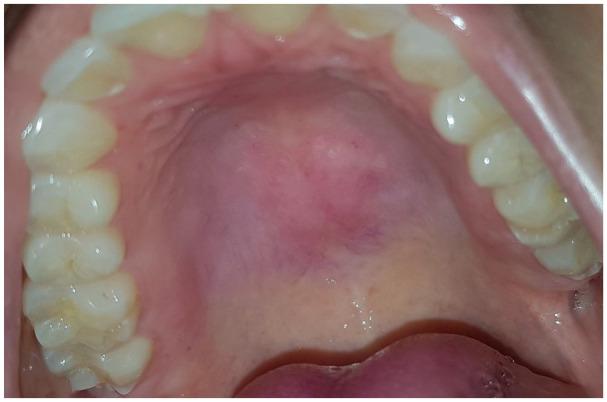

Thermal burns of the oral cavity usually arise from ingestion of hot foods or beverages. A 38-year-old female patient presented with two painful ulcerative erythematous patches of the palate. The patient was consulted on the same day lesions appeared. Medical history was unremarkable. Clinically significant self-inflicted injuries may result in wide ulcers in the mouth and usually do not take less than 2 weeks to heal, whereas our patient, treated with low-level laser therapy, had a complete response in day 4, after 2 days of treatment. The fact that multiple lesions were present signaled against the World Health Organization exclusion diagnosis of erythroplakia for red patches. A traumatic ulcer, regardless of its cause of origin, usually heals within 2 weeks, after the source of injury is resolved. A thermal burn in the oral cavity usually takes longer than that to heal, but whenever this time frame is not respected, the suspicion of a potentially malignant disorder should always arise, and a biopsy should be performed. The present case showed two painful thermal burns with great results in terms of speeding up the relieve of symptoms and healing time with soft laser as opposed to the traditional treatment with oral topical corticosteroid.

口腔热烧伤通常由摄入过热的食物或饮料引起。一名38岁女性患者腭部出现两处疼痛性溃疡性红斑。病变出现当天患者前来就诊。病史无异常。具有临床意义的自残伤可能导致口腔内出现广泛溃疡,通常愈合时间不少于2周,而我们的患者接受低强度激光治疗后,治疗2天后在第4天完全康复。存在多个病变这一事实排除了世界卫生组织对红斑性增殖性红斑的排除诊断。创伤性溃疡无论其起源原因如何,在损伤源消除后通常在2周内愈合。口腔热烧伤通常愈合时间更长,但只要不符合这个时间框架,就应始终怀疑可能存在恶性疾病,并应进行活检。本病例显示两处疼痛性热烧伤,与口服局部用皮质类固醇的传统治疗相比,软激光在加速症状缓解和愈合时间方面效果显著。